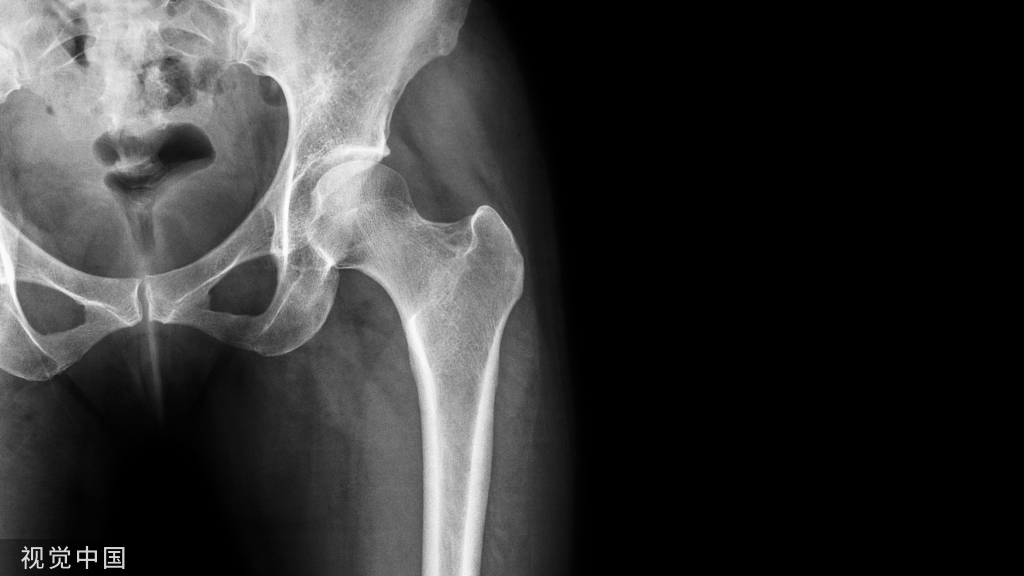

首页/骨科精读/从髋关节的解剖到手术入路全过程,你要的解答全在这!/

从髋关节的解剖到手术入路全过程,你要的解答全在这!

髋关节手术,对于大多数骨科医生来说都是复杂和高深的,因为他位置深在,结构复杂,今天我们就重点来学习髋关节的解剖和手术入路,值得学习借鉴!